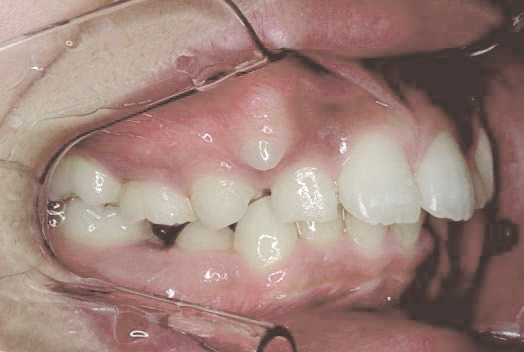

下方成長の症例のbefore/after

バイオブロック矯正は、歯だけではなく顔全体の発達に焦点を当てた矯正治療法です。顎の下方成長(顎が下へ下がるように発達すること)を防ぐことに重点を置き、正しい方向への成長を促します。顎が正しく発達することで、永久歯が生える前に、生えやすい場所に移動するため、治療期間の短縮につながります。

取り外し可能な器具を使用して顎や歯の位置を正しい向きに調整し、より自然な方法で歯並びを整えることを目指します。

主要な治療内容と効果:顎の成長のコントロール

バイオブロック矯正では、顎の成長を前方へ導き、下顎の後退を防ぎます。

歯並びだけを整えるのではなく、すべての歯が自然な位置で並ぶことができる顎を目指します。

これは、成長過程だからこそできる治療法です。歯並びが崩れにくい顎をつくることで、問題の根本解決につながる上に後戻りしにくく、矯正後のケアも少なく済みます。